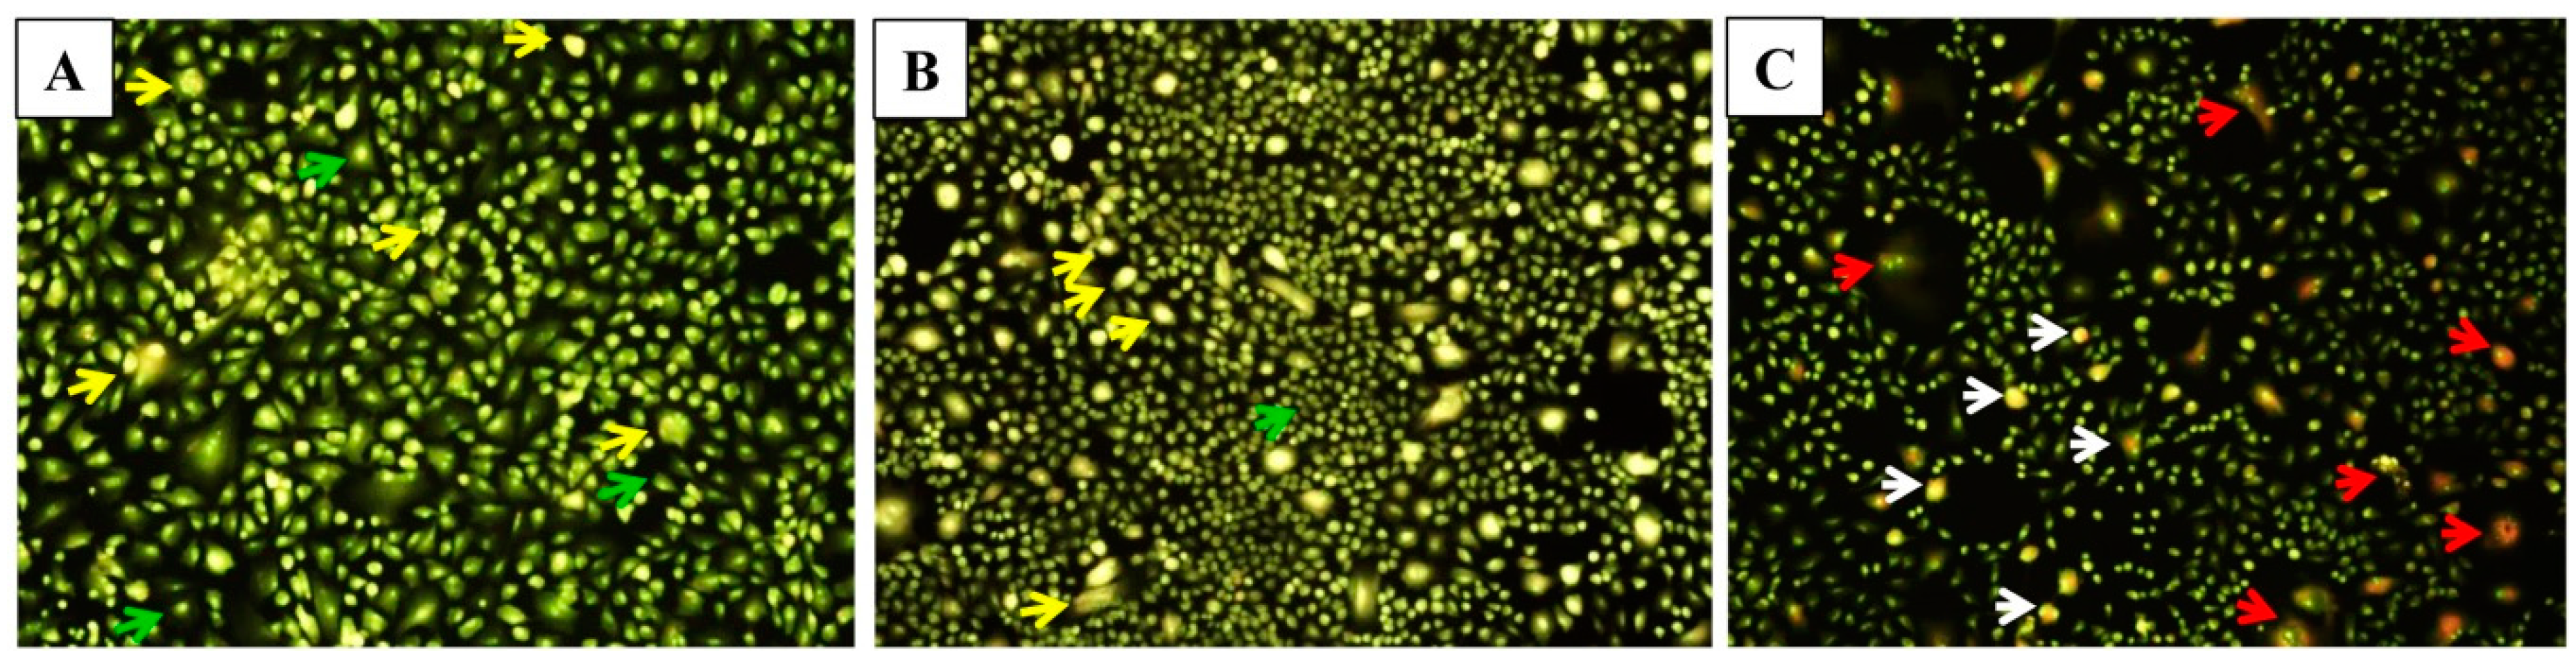

The hallmarks of cells undergoing apoptosis include cell shrinkage and rounding, surface membrane blebbing, chromatin condensation followed by nuclear fragmentation and cellular disassembly [35]. For the morphological analysis, selective fluorescent DNA binding dyes (such as acridine orange/ethidium bromide) methods are preferred owing to their simplicity, accuracy and rapidity. Such assays eliminate cell fixation step, thus eluding several potential artefacts [36]. In the present study, the induction of apoptosis after the treatment with modified nanoparticles determined by fluorescence staining using a DNA-specific dye. Acridine orange/ethidium bromide (AO/EtBr) staining was performed to investigate necrosis, chromatin condensation in the cells. Acridine orange can permeate the normal cell membrane, the cells were observed with green fluorescence. While yellow or orange coloured bodies were observed in apoptotic cells and apoptotic bodies which were formed due to nucleus shrinkage, chromatin condensation. Lastly, necrotic cells appeared as red coloured fluorescence owing to their loss in membrane integrity [37]. This dual staining facilitates to easily differentiate between early apoptotic, late apoptotic and dead cells, and also to detect mild DNA injuries [38]. In the present study, EPI-PTX combination drug and nanoparticles induce cell membrane blebbing, and chromatin condensation, indicating early apoptosis (Figure 6). While necrosis was observed in the cells treated with the PEI modified nanoparticles. The obtained results are in accordance with the previous studies. As shown earlier, the combined treatment with PTX caused higher apoptotic effect as compared with the individual drugs. Sharma et al. demonstrated that PTX in combination showed higher percentage of apoptotic cells when administered in MCF-7, MDA-MB 231 (human breast cancer cells) [39]. Also, in prostate cancer, it was shown that on treatment with combination drugs, there was a significant decrease in BCl-2 mRNA expression, and an increase in Bax (p < 0.05). The results further validated the nuclear irregularities and apoptosis which were observed microscopically.

Figure 6.

Microscopic images of A549 cells for apoptosis study. (A) Untreated A549 cells demonstrated normal structure (green arrows), early apoptosis (yellow arrows) such as chromatin condensation, cell membrane blebbing were observed after treatment with, (B) Free EPI-PTX and, late apoptosis (white arrows) and necrosis (red arrows) were noticed after treatment with, and (C) PLGA-PEI-EPI-PTX NPs, respectively.